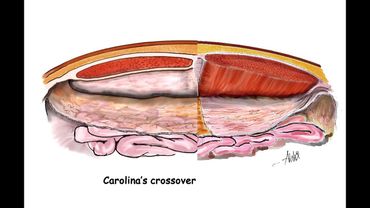

eTEP RS with midline crossover in hypogastrium for Primary Epigastric Hernia with divarication